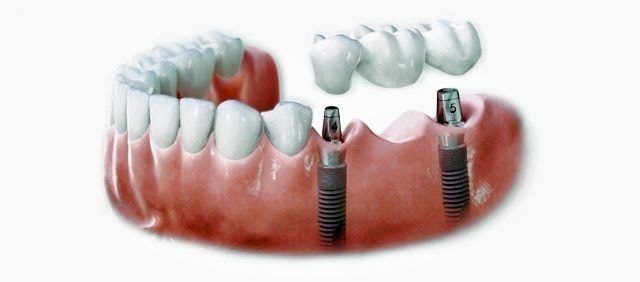

3本ブリッジ試算

インプラント2本  40+35万円  中間ダミー歯   10万円  合計85万円

3本ブリッジ